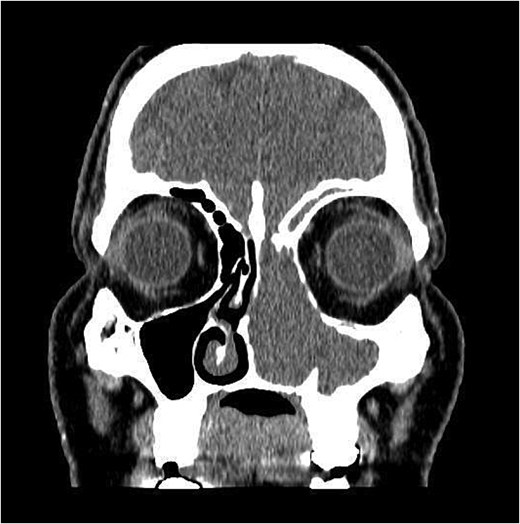

The patient underwent staging CT which was negative for distant metastasis. He then went underwent incomplete medial maxillectomy, ethmoidectomy, and sphenoidotomy followed by 10 sessions of immunotherapy abroad. He presented to our institution for follow up 6 months later with history of left nasal block and epistaxis. Nasal flexible scope showed a reddish nasal mass with greenish secretions (Fig. 3). Follow up CT revealed tumor recurrence (Figs 4 and 5). He was advised for multidisciplinary team evaluation to plan the treatment but he refused any intervention and lost follow up.

Coronal section of CT paranasal sinus soft tissue window showing the mass occupying the left nasal cavity and extending to maxillary and ethmoidal sinus, and reaching base of skull.